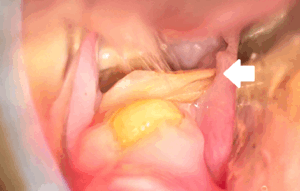

症例集 症例集:うさぎの不正咬合を更新しました。 2025.08.19 Tweet Share Hatena Pocket RSS feedly Pin it この記事のタイトルとURLをコピーする 症例集にうさぎの不正咬合を更新しました! こちらからご覧ください。 Tweet Share Hatena Pocket RSS feedly Pin it この記事のタイトルとURLをコピーする 犬猫の室内での熱中症対策 前の記事 指名予約始まりました! 次の記事